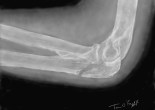

Fractures du cubitus/ulna – olécrâne, apophyse coronoïde, épine olécrânienne

L’extrémité supérieure du cubitus (ou ulna) a une forme particulière pour povuoir être articulée en haut avec la trochlée de l’humérus et latéralement avec la tête radiale. Le processus osseux … Lire la suite